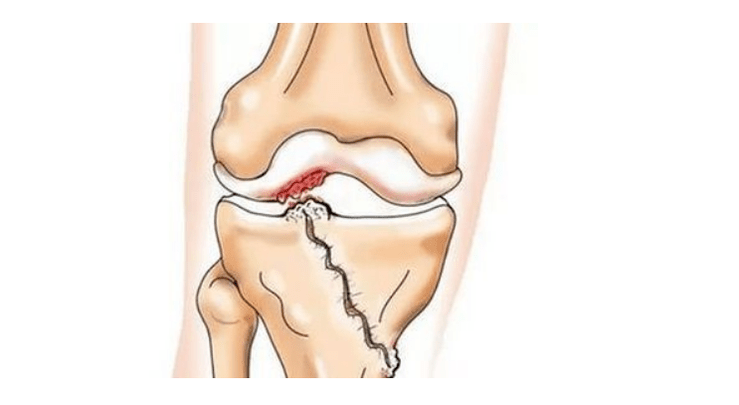

- Injuries (fractures, meniscus tears and anterior cruciate ligament).Unfortunately, in anyone, regardless of age, these injuries cause excessive stress on the cartilage.A fracture of any part of the bones covered with cartilage is accompanied by the formation of an unevenness - a "step".In this area, when moving, abrasion occurs and osteoarthritis forms;

- rheumatoid arthritis, Koenig's disease (osteochondritis dissecans), consequences of purulent inflammation in the joint (gonitis), etc.;